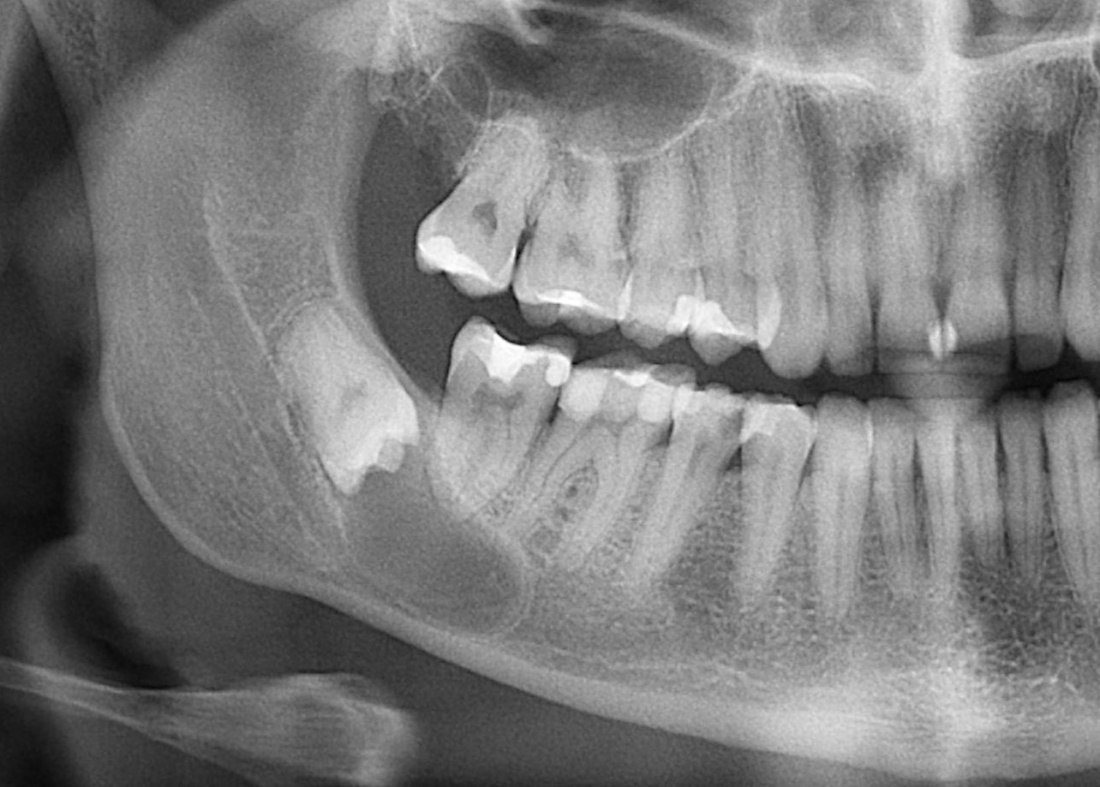

К нам в клинику обратился молодой человек с целью плановой санации: почистить зубной налет, вылечить кариес и т. д. Перед лечением ему сделали панорамный снимок. На снимке вот это:

Напомню, он пришел с целью плановой санации, а это значит, что ни зуб мудрости, ни киста. ни что-то там еще его не беспокоят. А теперь, внимание, вопрос ко всем вам:

— Нужно ли удалять зуб мудрости?

Следуя логике некоторых из моих коллег, а именно «если не беспокоит — не трогать«, этот зуб мудрости и кисту удалять не нужно. Не беспокоит же! Вот когда заболит, тогда придете! Слышали такие рекомендации? Я тоже слышал, причем неоднократно. Причем, от очень «авторитетных» (кавычки неспроста) специалистов.

Однако, если мы так все оставим, то, скорее всего, это приведет вот к такой ситуации, при которой мы всерьез будет рассуждать уже не только об удалении выросшей кисты и зуба, но и о сохранении соседних зубов и части нижней челюсти вообще. Скажет ли пациент «спасибо», когда узнает, что именно наше бездействие привело к таким результатам? Мы, конечно, в ответ можем помахать списком литературы и ссылками на «авторитетные» (кавычки неспроста) источники, но станет ли ему от этого легче? Вряд ли.

Вернусь к нашему клиническому случаю. Да, ни зуб мудрости, ни киста, которая из-за него возникла, нашего пациента не беспокоят. Тем не менее, все вы видите явные показания к удаления и ретинированной восьмерки, и кисты.

Что мы и делаем. До удаления я попросил нашего терапевта Михайлову Елену депульпировать соседний седьмой зуб, поскольку, по данным КЛКТ, его корни выходили в просвет кисты. Жалко, конечно. Но вот, такие коварные эти зубы мудрости.